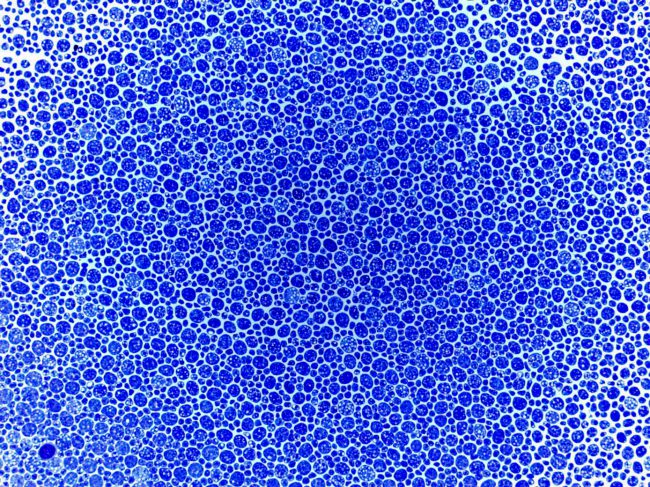

- Photoreceptor toxicity assessment

- Photoreceptor toxicity assessment